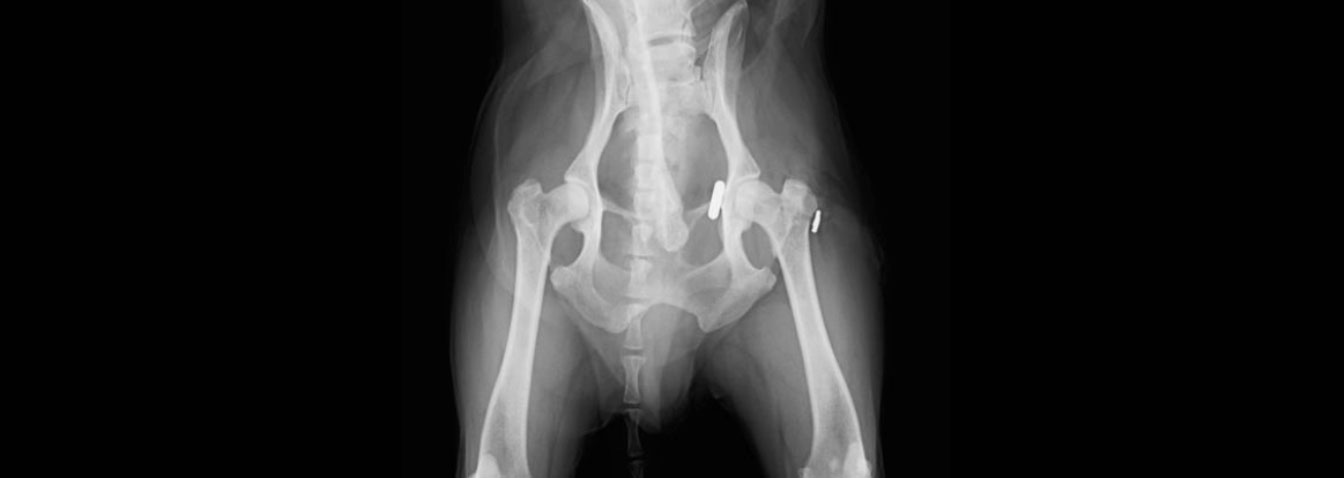

脱臼(術前)大腿骨が寛骨臼から大きく外れて関節機能が失われています